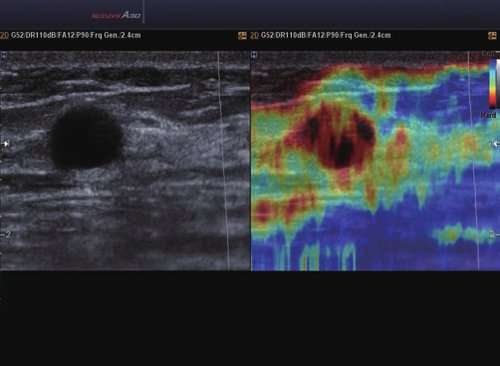

• ElastoScan™ ermöglicht eine genauere Visualisierung von Tumoren und erfasst und dokumentiert Gewebesteifheiten.